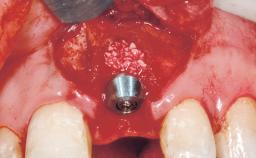

A 30-year-old female patient had lost tooth 21 and was referred to our clinic for consultation and treatment. Due to advanced apical infection, tooth 21 had been extracted two months earlier at another clinic and an acrylic-resin tooth had been bonded to the adjacent teeth. The patient desired implant treatment to avoid any damage to the adjacent natural teeth. While the patient had no history of any systemic disorder, she was a heavy smoker and exhibited medium to advanced periodontitis in the entire jaw. After the initial treatment to achieve a pocket probing depth of less than 4 mm and no bleeding on probing, a decrease in the height of the papillae mesial and distal to the extraction site and overall gingival recession were observed.

Type of Implants One-Piece|Reduced-Diameter

Bone Augmentation Horizontal|Staged

Augmentation Materials Autogenous chips|Membrane

Soft Tissue Grafting Simultaneous